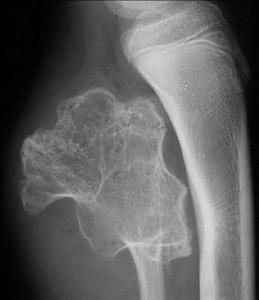

靠近皮質表面有明顯的軟組織腫塊陰影,可將其附近的骨皮質壓成一表淺缺損,骨表面顯示粗糙不平,可出現骨膜反應,骨髓腔內有硬化現象。病變內約有50%病例有明顯的鈣化。這些鈣化點常是診斷的重要線索。骨皮質表面的大段粗糙不平,常可被誤診為惡性腫瘤。

依據病史,臨床症狀、體徵、好發部位及典型的X線表現,即可診斷骨皮質旁軟骨瘤。